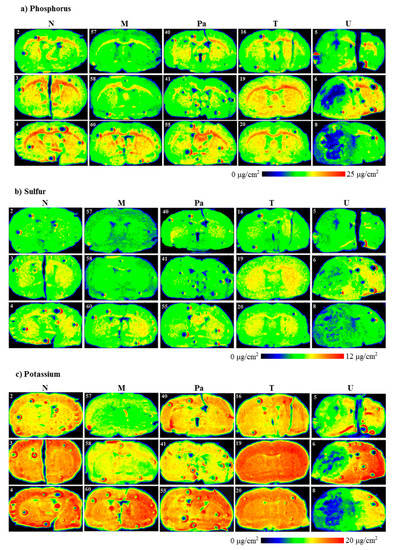

Evaluating the distributions of the elements under interest (P, S, K, Ca, Fe, Cu, Zn and Se) in the scanned brain slices was the first step of our investigation. The results of the topographic elemental analysis for the representative samples that originated from all the experimental groups are provided in Figure 3.

Figure 3.

Topographic elemental maps of brain slices taken from the rats of all experimental groups for: (a) phosphorus, (b) sulfur, (c) potassium, (d) calcium, (e) iron, (f) copper, (g) zinc and (h) selenium. Color scales express areal densities of elements in μg/cm2. In the case of Ca, large differences in areal densities were observed between groups N, M, Pa, T and group U. Two different scales were applied for better visualization of the distribution of this element.

As one can see from Figure 3a, a clear decrease in P accumulation in the implanted brain hemisphere and especially in the area of tumor development was found for the rats from the U group. A reduced element content was noted compared to the naive hemisphere within the same sample, as well as compared to the left hemisphere of the normal animals. A similar relation was observed for the animals implanted with patient-derived glioma cells. Additionally, for them, the area of the tumor determined from microscopic examinations corresponded with the region of a slight decrease in phosphorus accumulation. In the case of groups M and T, we did not observe any changes in P distribution in the regions of interest.

Topographic analysis of the maps of S distribution (Figure 3b) illustrated changes in the accumulation of this element in the left hemispheres of the animals implanted with the U87mg cells. For this group of rats, the areas of the reduced S content, compared to the intact hemisphere as well as to the left hemispheres taken from the control rats, were observed. These differences were not found in the case of the remaining experimental groups. A similar observation was made in the case of K distributions. The clear decrease in its accumulation occurred only in the areas corresponding to the tumors developed in the brains of the animals from the U group.